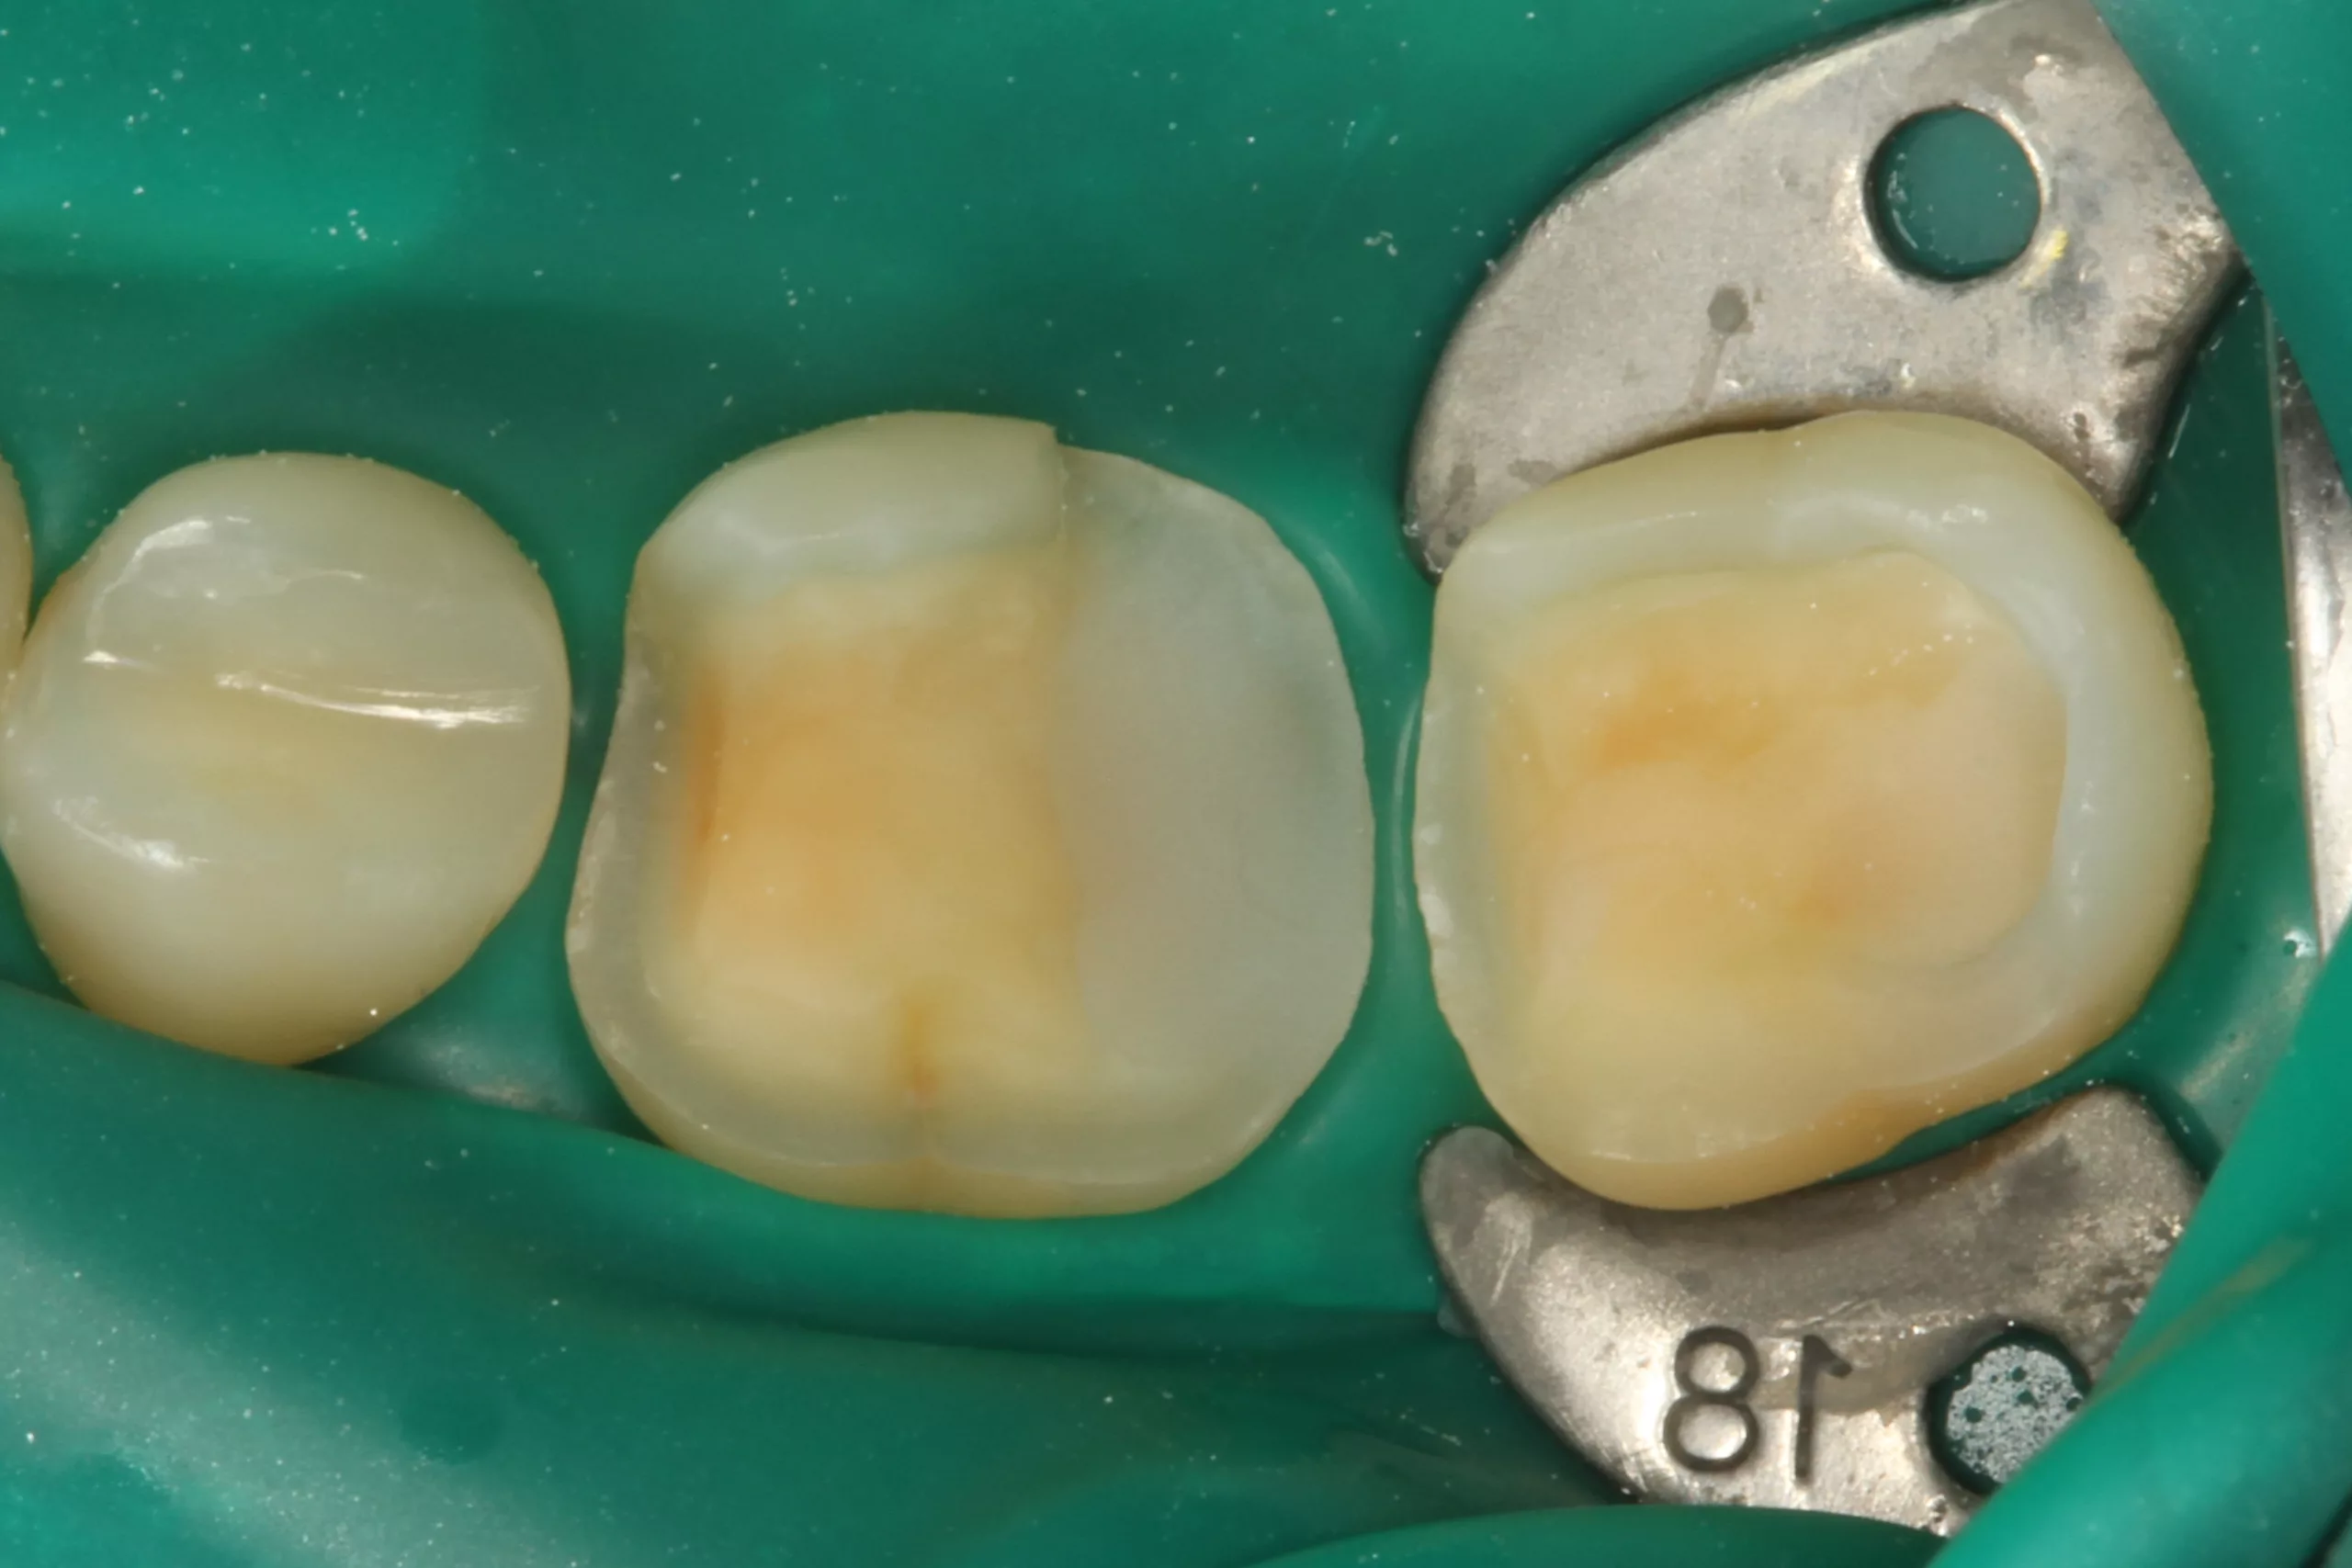

Bei der 42-jährigen ärztlichen Kollegin waren insuffiziente, größere Kompositrestaurationen mit z.T. Höckerersatz an den Zähnen 46 und 47 auszutauschen. Die Wahl fiel aus ästhetischen Gründen auf eine Lithiumdisilikatkeramik (IPS e.max Press, Ivoclar Vivadent). Die Farbbestimmung erfolgte chairside durch einen der praxiseigenen Zahntechnikermeister. Die Abbildung 1 zeigt die fertiggestellte Laborarbeit auf dem Arbeitsmodell. Die entscheidende Vorbehandlung der Keramik ist im Anschluss an die Einprobe die Reinigung der Keramik mit Ivoclean oder Phosphorsäuregel [10] und die anschließende Flusssäurekonditionierung. Die 5%ige Flusssäure stellt nach wie vor die am besten bewährte Vorbehandlungsmethode für glasbasierte Keramiken dar [1,12,14, 36,51,61,73]. Eine Meta-Analyse aus dem Jahr 2015 bestätigt dies [69].

Nach der Schmelzkonditionierung mit dem Phosphorsäuregel und dem ausreichenden Spülen für 15 Sek. ist für eine suffiziente volladhäsive Anbindung ein Benetzungsmittel, ein „Tooth Primer“ erforderlich. Der zu Visalys CemCore gehörende Visalys Tooth Primer ist ein selbstkonditionierender Einkomponenten-Primer, der keiner separaten Lichthärtung bedarf und somit die Ansprüche an die Selbsthärtung des Adhäsivs, die anschließend im Kontakt mit Visalys CemCore abläuft, erfüllt. Die Abbildung 3 zeigt die Einwirkung des Visalys Tooth Primers auf die Präparationsflächen der beiden Zähne 46 und 47. Die Befestigung der Teilkronen erfolgte gleichzeitig mit Visalys CemCore in der Farbe Universal (A2/A3), das vorab direkt auf die Teilkronen und nicht in die Kavitäten appliziert wurde (Abb. 4). Obwohl eine „Tack Cure“-Technik-Option zur Verfügung steht, wurden die Überstände des Befestigungsmaterials mittels Modellierspatel, frischem Bondingpinsel und Zahnseide entfernt. Die im Vergleich zu herkömmlichen Befestigungskompositen etwas höhere Konsistenz und bessere Standfestigkeit (kommt primär der Funktion als Stumpfaufbaukomposit zugute) erleichtert die Überschussentfernung immens, da das Material nicht so schnell unkontrolliert wegfließt. Es erfolgte eine initiale Härtung mittels eines Hochleistungs-LED-Polymerisationsgerätes. Zur Verhinderung der Sauerstoffinhibitionsschicht kann jedes herkömmliche Glyceringel verwendet werden. Alternativ kann die ebenfalls von Kettenbach angebotene Visalys CemCore Try In-Paste zur Anwendung kommen. Obwohl Visalys CemCore eine ausgezeichnete Selbsthärtung aufweist, erfolgte dennoch eine Lichthärtung unter Glyceringel für 20 Sek. pro Fläche. Die Überprüfung der statischen und dynamischen Okklusion darf erst nach Abschluss der Dunkelhärtung vorgenommen werden, damit die adhäsive Integration nicht gestört wird, wenn im Polymerisationsprozess durch Exkursionsbewegungen mechanisch auf die Klebefläche eingewirkt wird.

Die Abbildung 5 zeigt das klinische Endergebnis bei einer Kontrolle nach 2 Monaten: Die beiden Lithiumdisilikat-Teilkronen fügen sich ästhetisch harmonisch in die umgebende Zahnhartsubstanz ein. Das Befestigungskomposit verbindet Zahnhartsubstanz und Restauration perfekt, zeigt keinerlei Verfärbungstendenz und lässt sich farblich weder von der Restauration noch von der Zahnhartsubstanz differenzieren. Klinisch zeigten sich keinerlei postoperative Beschwerden und eine hochzufriedene Patientin.